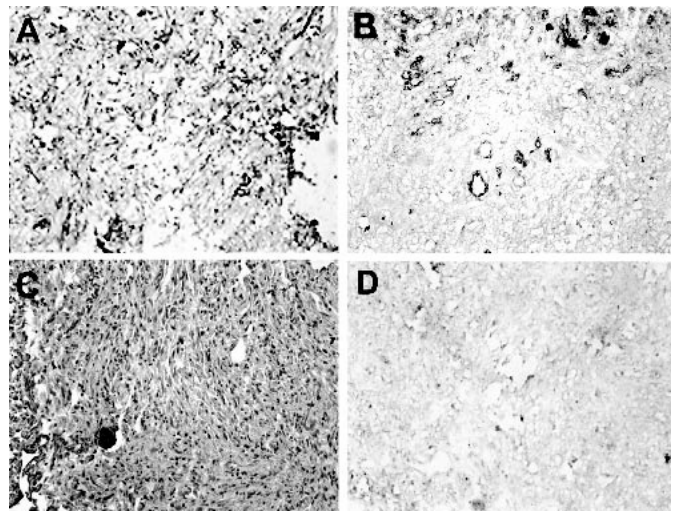

圖示:顯微照片(原放大倍數,200)顯示Gb3在人腦膜瘤中的免疫組化染色。(A)惡性腦膜瘤,表現為很強的(+ + +)Gb3免疫反應性(棕色),其染色處為血管外和血管外。(B) A MM半定量為強染色(+ + +),主要是由于Gb3的主要血管定位。(C)良性腦膜瘤,無Gb3陽性的證據。(D)當省略VT1時,A MM(與B相同)無Gb3免疫反應。